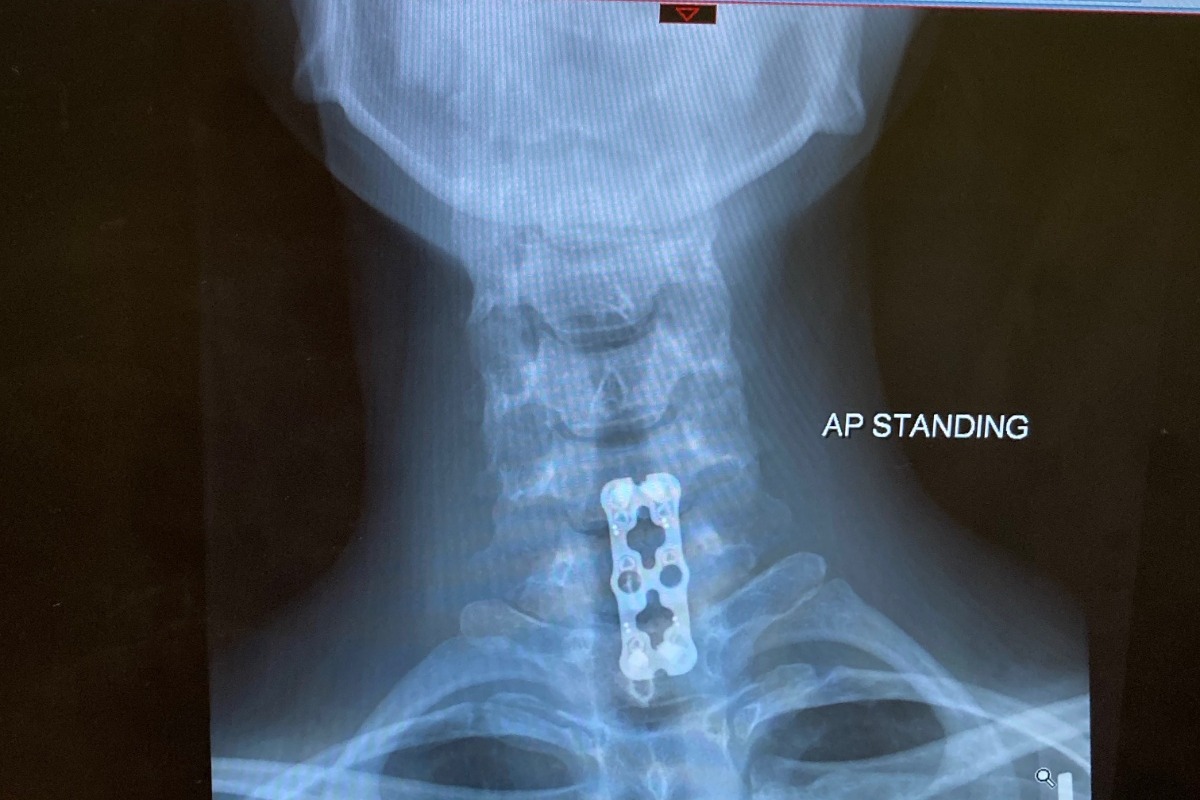

Just another ordinary day on the farm… until an angry momma cow decided she did not want me to tag her new baby calf. After being head butted, and flipped several times, with adrenaline pumping, I crawled on my hands and knees under the electric fence and into the safety of the next field. I was in a lot of pain and I knew something was wrong, but I thought I had just broken a few ribs. With great effort, I forced myself to stand and to walk (about a ½ mile) to my truck. I then drove down the bumpy lane to the closest neighbors’ house for help. As my pain was increasing, the kind neighbor insisted I go to the hospital and she promptly drove me to the local ER, where I was quickly immobilized. A Spine Specialist was then called in, and after looking at my x-rays, I was told they needed to transfer me to a hospital that was better equipped to treat my injuries. After I was transferred, they performed many more tests and scans. Anxiously, I waited for the news…. First, the Dr. told me that I had broken my neck (Cervical spine fracture/Closed displaced fracture of seventh cervical vertebra) and would need surgery the next morning…. Second, he also informed me that one of the scans showed a large suspicious mass in my chest wall cavity. I was stunned. The team of medical Drs. all said they were completely amazed that I had walked through the field in my condition and told me that I should be paralyzed. They also said I was truly “lucky”... but I knew it wasn’t “luck” at all. God was looking out for me.

broken neck  did NOT really fit into my life plan, and neither did a suspicious mass. I had to wait several weeks for a biopsy to tell us more. As I recuperated from my neck injury and was unable to work for the next 6 weeks, I resisted the urge to complain, but it was a very difficult task.